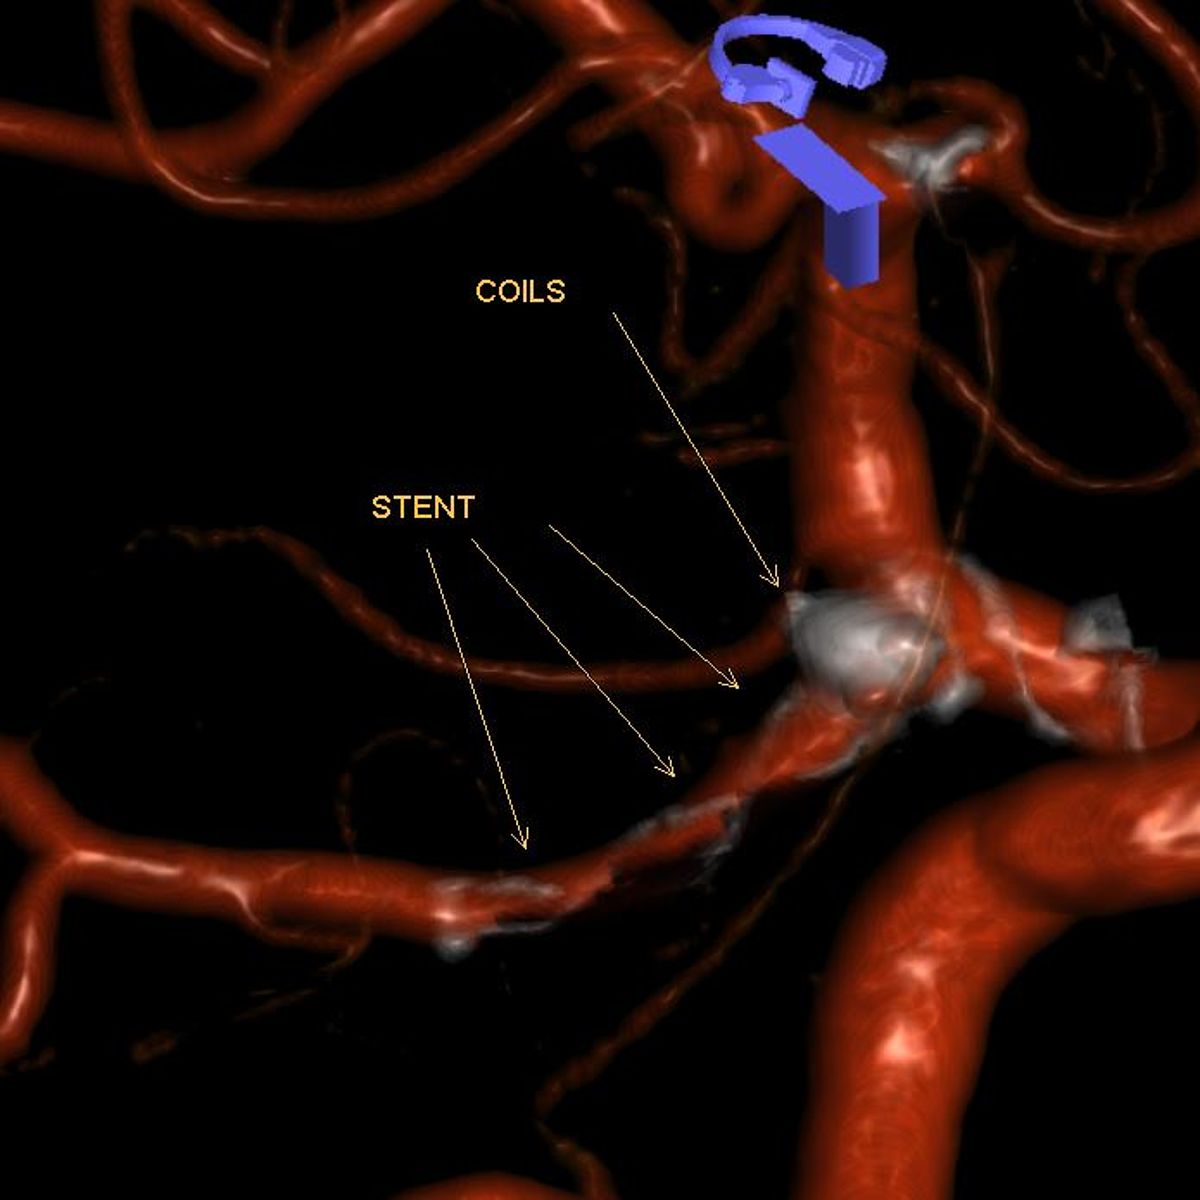

In Augsburg werden im Jahr etwa 80 solcher akuter Subarachnoidealblutungen behandelt. Dabei ist neben der Behandlung der Blutungsfolgen vor allem die Ausschaltung des ursächlichen Aneurysmas dringlich, was meist interventionell durch die Neuroradiologie erfolgt.

- Wie kann es behandelt werden?